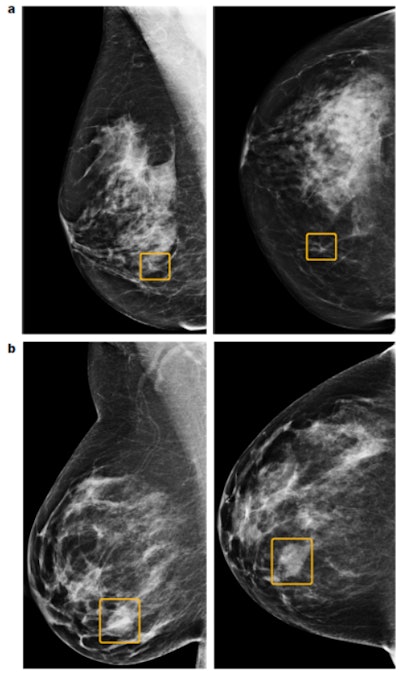

"The development of AI should be directed toward finding tumors according to their specific imaging biomarkers," he told AuntMinnieEurope.com on 2 January. "These include the more easily recognizable stellate and spherical tumor masses, but, more importantly, the subtle architectural distortion caused by the diffusely infiltrating breast malignancy of mesenchymal origin (also known as diffuse invasive lobular carcinoma), which is highly fatal and often missed at mammography."

Similarly, cancers developing within the major ducts may cause a massive and often fatal tumor burden as a result of new duct formation (neoductgenesis), which is difficult to detect on the mammogram before it calcifies, Tabár added.

Overall, AI has a great potential to help solve the complex issue of screening asymptomatic women, and it is necessary to be optimistic but also cautious about the potential for AI in real-life breast cancer screening, he noted. The primary purpose of screening is to find and treat the potentially fatal cancers when they are still in a curable stage.